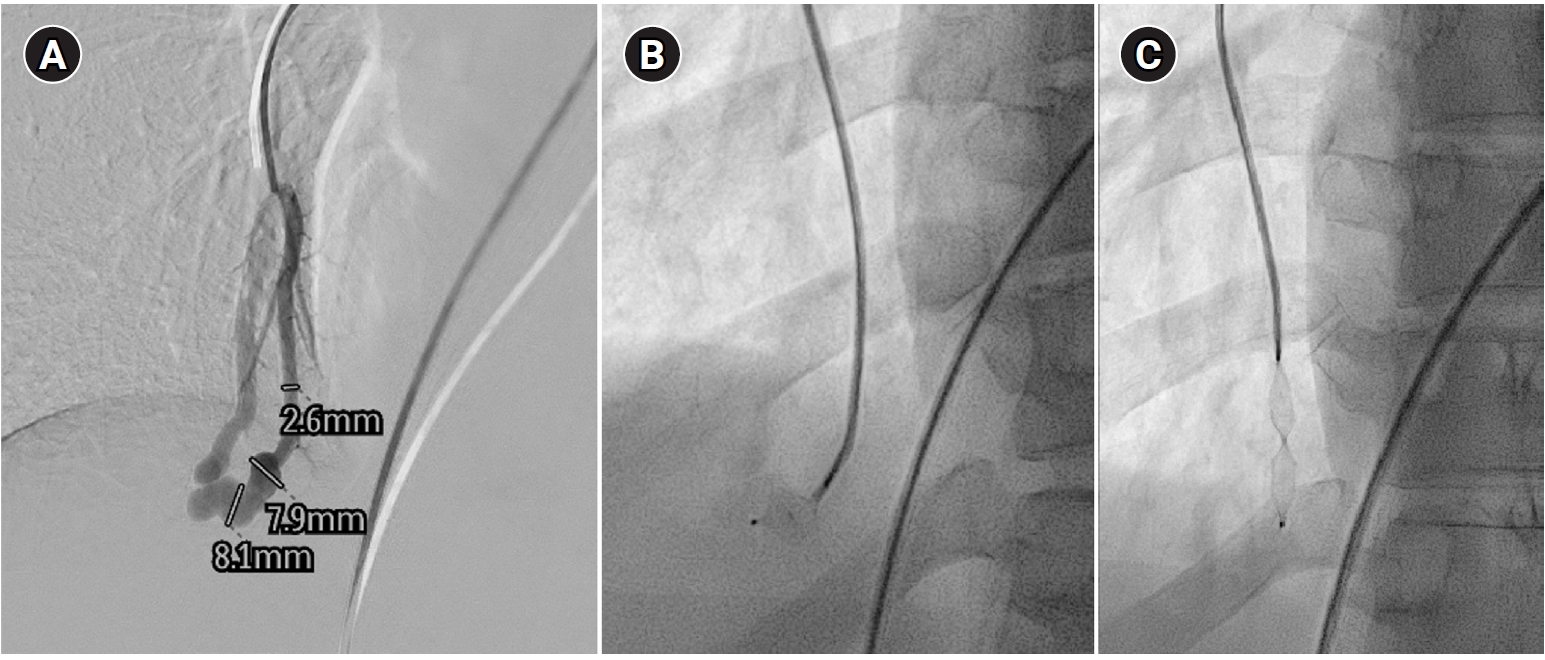

Fig. 5.

Embolization procedure in a patient with a feeding artery diameter of 2.6 mm and a venous sac diameter of 8 mm in the right lower lobe. (A) Selective angiography of the right lower lobe pulmonary arteriovenous malformation. (B) A 7 mm Amplatzer vascular plug type IV (arrow) was deployed into an approximately 8 mm venous sac, and it was determined that this would not provide adequate embolization effect. (C) By repositioning the Amplatzer plug and deploying it at the distal part of the feeding artery (arrow), it becomes clear that an Amplatzer vascular plug sufficiently larger than the feeding artery’s size is needed to effectively achieve embolization.

Historically, detachable balloons were used as an embolization material; however, they are no longer utilized in current practice [18]. In the context of PAVM embolization, the use of coils, vascular plugs, or a combination of both is now standard practice [19-21]. Since the development of detachable coils, they have offered advantages over pushable coils, particularly in terms of repositioning during the procedure. They can even be fully retrieved and redeployed if necessary, enhancing procedural safety and control. It is crucial to prioritize minimizing the recanalization rate while ensuring the overall safety of the procedure when selecting the appropriate embolic materials and techniques. Feeding artery coil embolization was historically regarded as the standard approach, whereas venous sac embolization was discouraged because of the perceived risk of rupture [22]. However, with the introduction of newer venous sac embolization techniques, recent findings now indicate that tightly packing the venous sac with coils can achieve a higher success rate than the traditional feeding artery approach (Fig. 2) [22-25]. Additionally, vascular plugs, including micro-vascular plugs (Medtronic, Minneapolis, MN, USA) and Amplatzer vascular plugs (Abbott Vascular, Saint Paul, MN, USA) have also demonstrated a higher success rate compared to feeding artery coil embolization (Fig. 4) [26-28]. In the case of vascular plugs, the risk of device migration is relatively low. Moreover, an additional advantage is that the device can be repositioned if the sizing is not ideal or if it is not deployed in the exact desired location. This flexibility enhances the precision of the procedure (Fig. 5). In a recent European guideline, there is also a recommendation to consider vascular plug embolization as a first-line option whenever possible, rather than coil embolization [11]. Additionally, a recent meta-analysis recommended vascular plugs or venous sac coil embolization, noting that vascular plugs had a recanalization rate of 13.6% compared to 32.7% for coil-only embolization. Similarly, venous sac embolization showed a 3.8% recanalization rate, while feeding artery embolization had a rate of 24.3%. Additionally, a recent meta-analysis has recommended the use of vascular plug or venous sac coil embolization, as these techniques have demonstrated a lower persistence rate compared to other methods [21]. This shift is largely in response to the relatively high recanalization rate associated with feeding coil embolization. In the case of embolization using vascular plugs, the plug should be deployed at the most distal segment of the feeding artery just before the venous sac in order to preserve the normal pulmonary artery. Since the pulmonary artery contains less elastin and has a thinner wall compared to systemic arteries, it is more distensible [29]. Therefore, in the author's experience, oversizing by about 50% to 100% has been effective in reducing the recanalization rate. When performing venous sac coil embolization, it is important to use coils large enough to create a stable framing coil larger than the draining vein diameter, thereby preventing coil migration. After establishing this frame, the venous sac and the proximal feeding artery should be carefully packed to achieve complete occlusion.